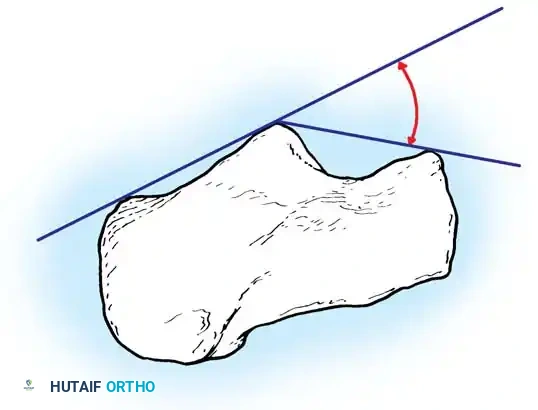

Böhler's Angle

The Böhler angle is formed by the intersection of two lines on the lateral radiograph: one drawn from the highest point of the anterior process to the highest point of the posterior facet, and another from the highest point of the posterior facet to the highest point of the calcaneal tuberosity.

A normal Böhler angle ranges from 25° to 40°. In intraarticular fractures, this angle is typically flattened or reversed, indicating severe collapse of the posterior facet and loss of calcaneal height.